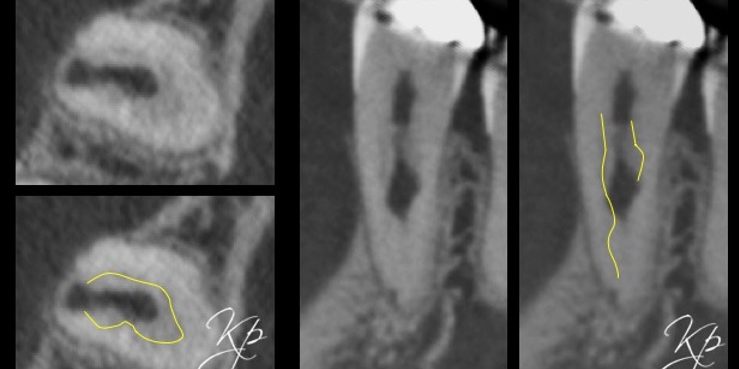

It is also the reason resorptive channels are seen progressing circumferentially around the root canal system (Figure 1).

Odontoclasts will invade around this layer and circumferentially around the root canal. As a result, the pulp can stay healthy until late in the process.

External cervical resorption typically presents as an asymmetrical radiolucency with irregular borders (Figure 4).

The outline of the root canal is visible through the lesion indicating the resorption is on the external aspect of the tooth.

Figure 5: From the PA radiograph LR5 has the classical appearance of internal resorption.

However, the CBCT scan shows the resorption is external cervical resorption.

The resorption starts buccally at the cervical margin. It extends down the root and spreads 360º around the root canal.

We often see this appearance because the canal is surrounded by a protective predentine layer, which is more resistant to resorption